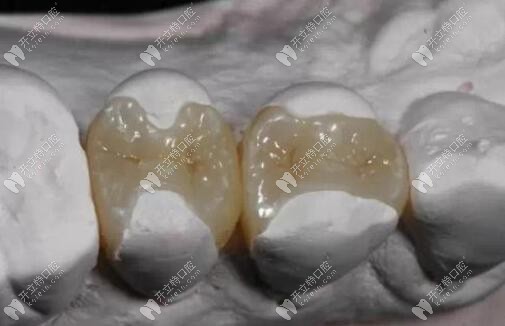

嵌體圖片

嵌體

嵌體補牙圖片

嵌體補牙